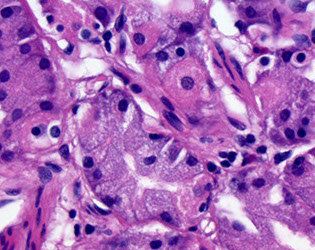

GastroIntestinal Stromal Tumor (GIST)

MC mesenchymal tumor of the abdomen, usually in muscularis propria; vary in px and differentiation according to location in GI

- 60% in stomach, 30% in sm intestine; 1/4 are malig

Peak age is 60 years; 1/2 present c mets

- can be found in 1/3 resected stomachs

- if found in female kiddos, think Carney's triad: GIST, extra-adrenal paraganglioma and pulmonary chondroma

- was thought to be of sm muscle origin, even though no sm muscle was seen on EM

- Arise from cells of Cajal (pacemaker cells)

Micro: usually spindled, but can be epithelioid (and cause confusion)

- spindly tumors have palisading, paranuclear vacuoles, collagen fibrils

1/10 are epithelioid GISTs, 3/4 are b9;

- larger tumors in fundus or cardiac more likely to be malig

- up to 3/5 met, usually w/in 2 yrs; which has 8 mo avg survival

- inc prolif and necrosis may have worse outcomes

- also has worse outcome if it invades into mucosa

Genes: 4/5 have gain-of-function of tyrosine kinase KIT

- CD117 mutation at exon 11 (???)

2 types of KIT mutation groups: regulatory site type (which allows binding of imatinib) and enzymatic site mutation (which prevents binding of imatinib)

-- pts may develop resistance to imatinib

~ 5-10% of GISTs do not have KIT mutations and are assoc c PDGFRA mutations (require different tx)

Succinate dehydrogenase (SDH)-deficient GIST

If the GIST does not have KIT or PDGFRA mutations, consider germline loss of SDH (succinate dehydrogenase complex) assoc c Carney-Stratakis syndrome: GIST and paraganglioma; which is distinct from Carney triad (although SDH-def GISTS also assoc c Carney triad). Both have loss of SDHB expression by IHC

- SDH deficienct GIST is aka "pediatric type GIST" (bc is the MCC GIST in kiddos) and is usually plexiform/multinodular; usually more epithelioid; very rare in pts > 40 yo

- IHC: loss of SDH subunit B (SDHB) expression, but are still CD117 and DOG1+

Grading ***5-5-10-50!!***:

Benign: <5 cm, <5 mits/ 50 hpf

Uncertain malig potential: cellular, <5 cm, >5 mits/ 50 hpf

Low-grade gastric GIST: cellular, >5 cm OR <10 mits

High-grade: cellular, any size, >50 mits

IHC: (+) CD117 (98%), c-kit, DOG1 (Discovered On GISTs), CD34 (7/10), bcl2, actin (3/10)

- rare cases can be CD117 negative (3/4 have PDGFRA mutation, 1/10 have KIT mutation)

- suggested panel: CD117, CD34, SMA, desmin, CK, S100, melanA, DOG1, SDH

Genes: 96% express c-Kit (CD117/34)

- activating mutations in KIT genes (esp exons 11>9>13/17)

- PDGFRA mutations assoc c epithelioid morphology

- some can have BRAF or NF1 mutations

- assoc c NF1 in sm intestines, which is KIT wild type (no mutations) but still is CD117+

Tx: imatinib meslate (inhibitor of speciic tyrosine kinases [targets PDGFr]) effective in metastatic GISTS (also in CML)

- mutation in KIT exon 11 is highly assoc c imatinib response; mutations in exons 9, 13, and 17 are somewhat less likely (40-50%) to be imatinib sensitive; tumors c no KIT mutation may be imatinib sensitive in up to 30% of cases

- the MC PDGFRA mutation (D842V) is completely insensitive to imatinib, while others may be responsive

Px: most important are size, mits and location of primary lesion (stomach best, then small intestestine, then colorectum)

- 1/5 are malig; poorer px if >5 mits/50 hpfs or >5 cm

- 2/5 5-yr survival; surgery not really proven to help

Epithelioid GIST

Spindle-celled GIST

GIST grading